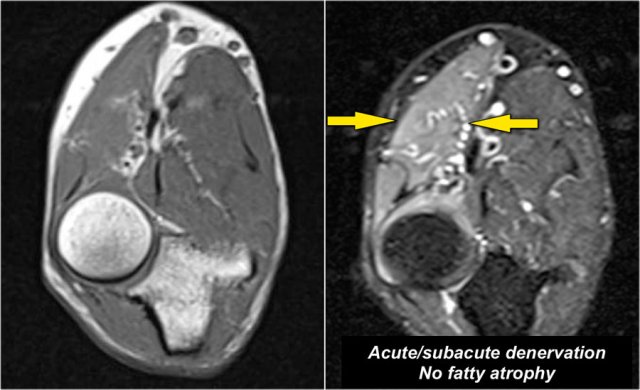

Denervation

Nerve pathology can present as thickening of the nerve when there is neuritis or as a result of compression of the nerve.

A secondary sign of nerve pathology is denervationwith edema and/or atrophy of the muscle.

In this case there is chronic atrophy with high sinal on T1, which is irreversible.

In early or subacute denervation the prominent sign is edema with high signal on T2W-images and that is reversible.

This is a 48 year old male with Marfan's syndrome, who had a sudden onset of right hand weakness.

This is a nice example of subacute denervation.

Notice on the T1W-image that there is no atrophy.

Only edema on the T2W-image.

This was due to proximal radial neuropathy.